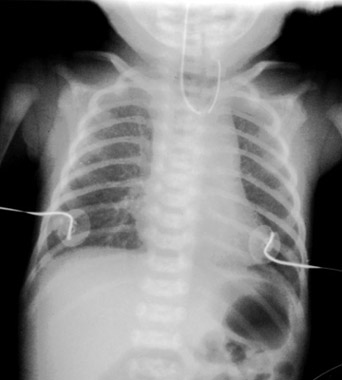

Pediatric Radiology > Abdominal > Neonatal > Esophageal Atresia (2)

Esophageal Atresia - Radiographic Features

Common radiographic features include the "Coiled NG Tube" in the esophageal pouch. If there is bowel gas in the abdomen there must be an associated tracheoesophageal fistula, ~90% of cases of esophageal atresia. A TE fistula can occur without esophageal atresia and may present later in life with wheezing or recurrent pneumonia. |